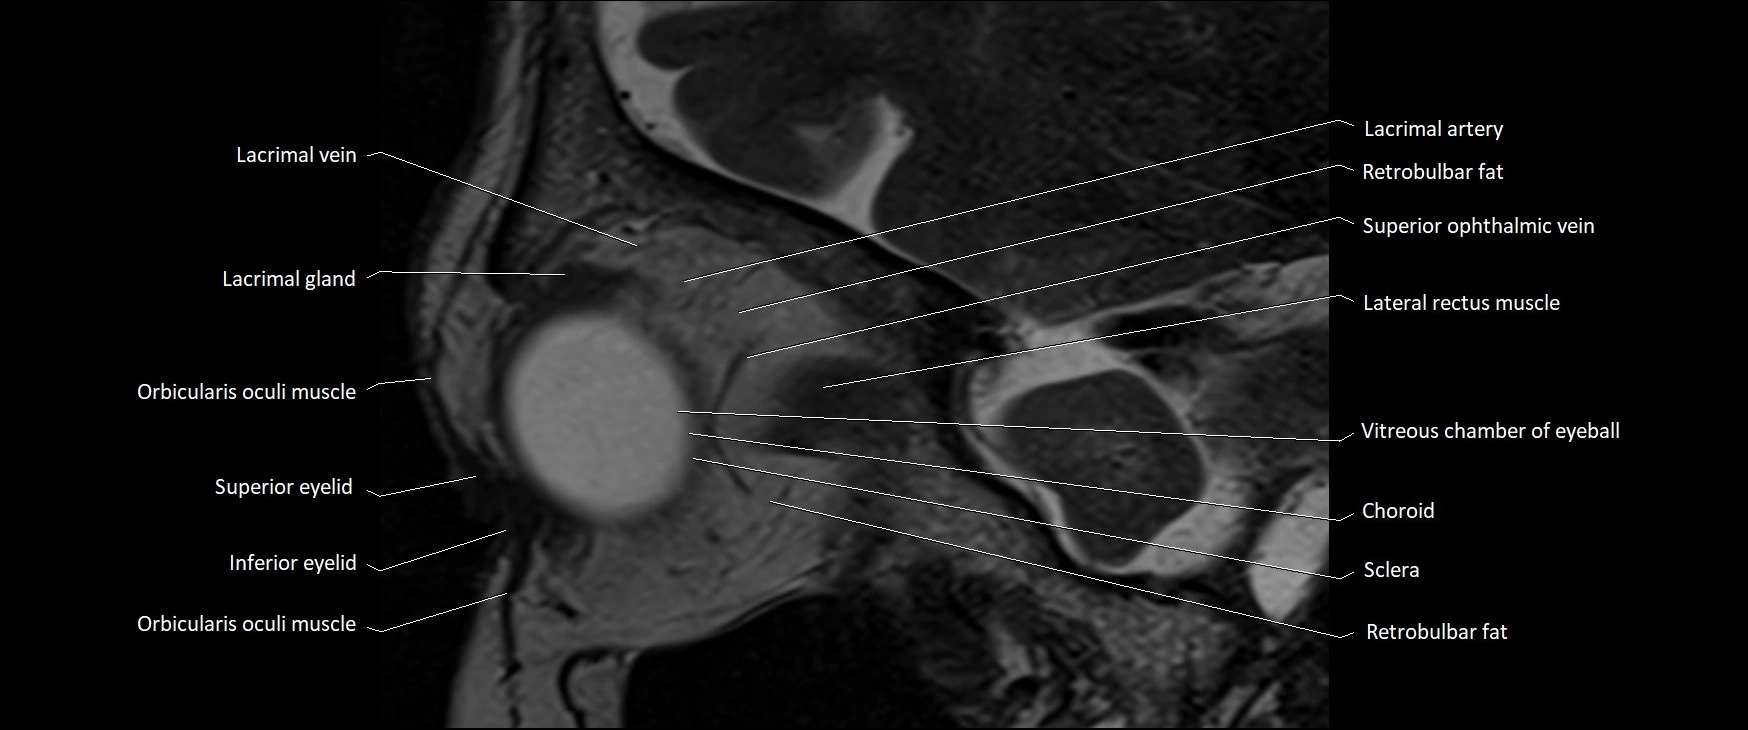

MRI images